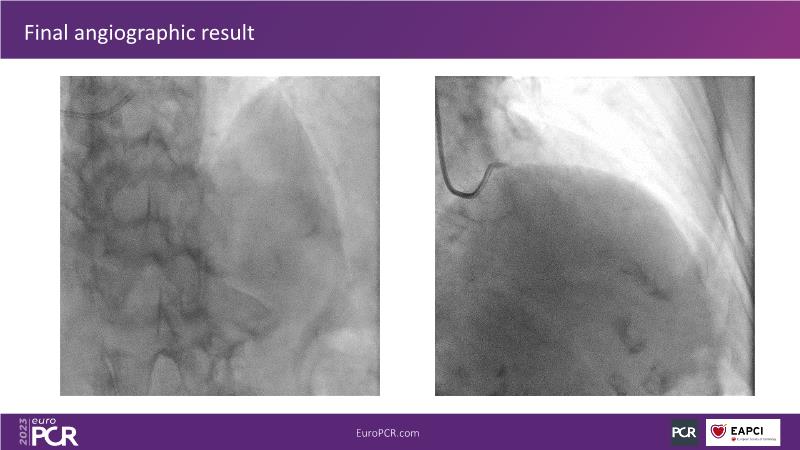

Join this session to explore the advantages of a fully optical approach in optimizing percutaneous coronary intervention (PCI) with the OptoWire III physiology wire and Nipro HF-OCT catheter. Through a practical case, you'll discover the significance of coronary physiology and intravascular imaging in bifurcation PCI and gain insights into how the performance and accuracy of the OptoWire III physiology wire can facilitate fast and reliable decision-making, particularly in side branch jailing scenarios.

- To discover the benefits of a fully optical approach to optimise PCI with OptoWire III physiology wire and Nipro HF-OCT catheter

- To review, through a practical case, the value of coronary physiology and intravascular imaging in bifurcation PCI

- To understand how the performance and accuracy of OptoWire III physiology wire can make the difference for fast and reliable decision-making in bifurcations, particularly through side branch jailing